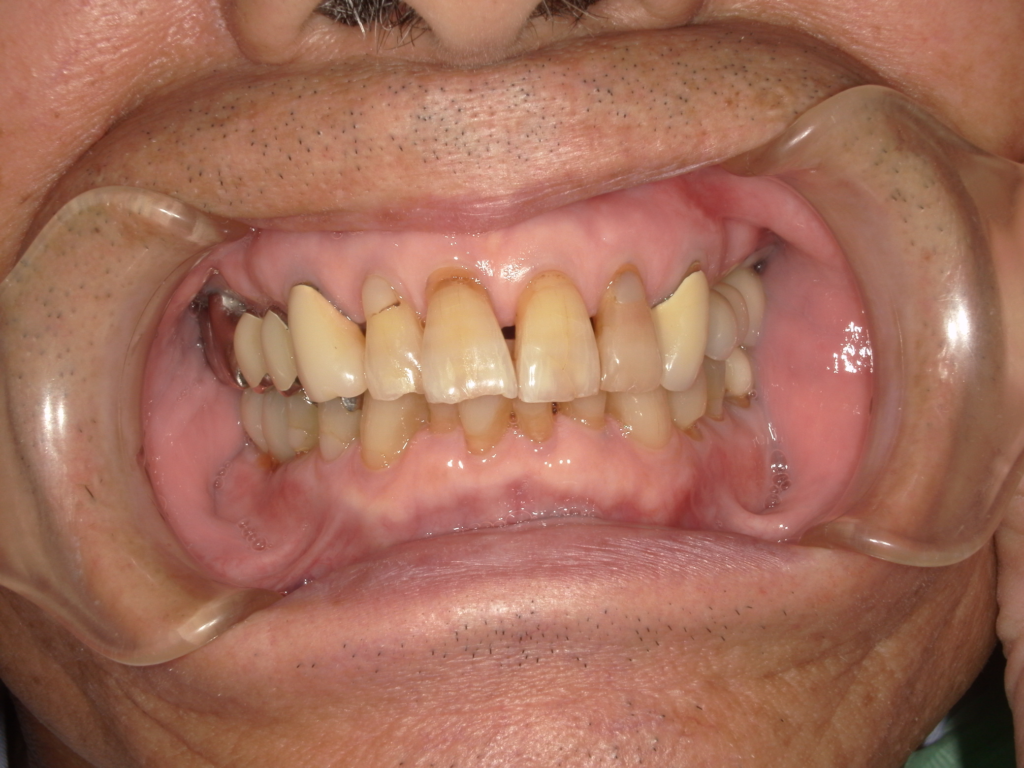

Y様インプラント実例 #44

左の上下の奥歯をインプラントで治療しています。

左下の奥歯は歯を抜くのと同時にインプラントの埋め込みを行っています。

被せものは上下、セラミックスで作っています。

治療前

治療後